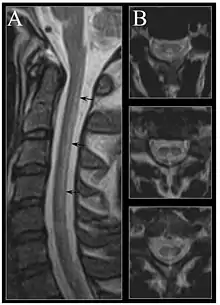

| Image of the cervical spinal cord in vitamin B12 deficiency showing subacute combined degeneration. (A) The midsagittal T2 weighted image shows linear hyperintensity in the posterior portion of the cervical tract of the spinal cord (black arrows). (B) Axial T2 weighted images reveal the selective involvement of the posterior columns. | |

MRI of the brain may show periventricular white matter abnormalities. MRI of the spinal cord may show linear hyperintensity in the posterior portion of the cervical tract of the spinal cord, with selective involvement of the posterior columns.